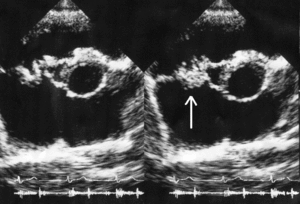

| A mitral valve vegetation caused by bacterial endocarditis. | |